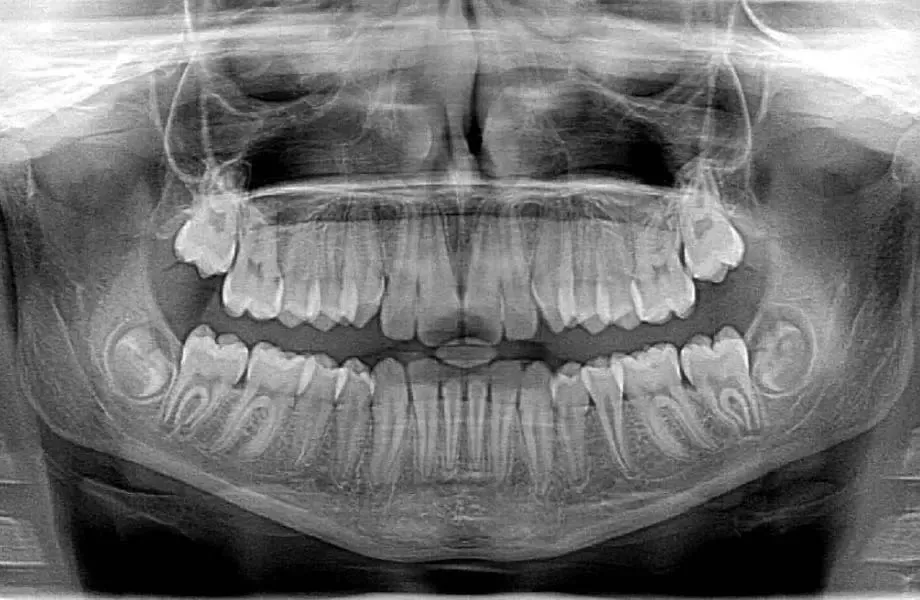

Panoramic X-ray (OPG)

A panoramic scan captures a complete view of the entire mouth, including all teeth, jawbones, and surrounding structures. It is commonly used for treatment planning before procedures such as orthodontics, wisdom tooth extraction, or implants.

Estimated cost: PHP 800 – PHP 2,500, with many clinics charging around PHP 1,000 – PHP 1,500.